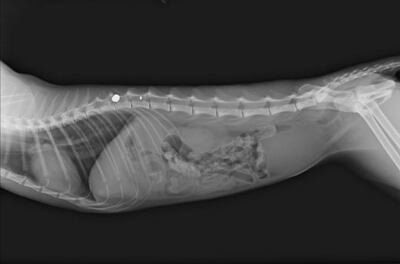

X-rays showed the bullet had hit the cranial lumbar vertebrae, or mid-spine.

The gruesome act caused such severe injuries that the animal had to be euthanised. Its hind legs were paralysed and X-rays showed the bullet had hit its spine.